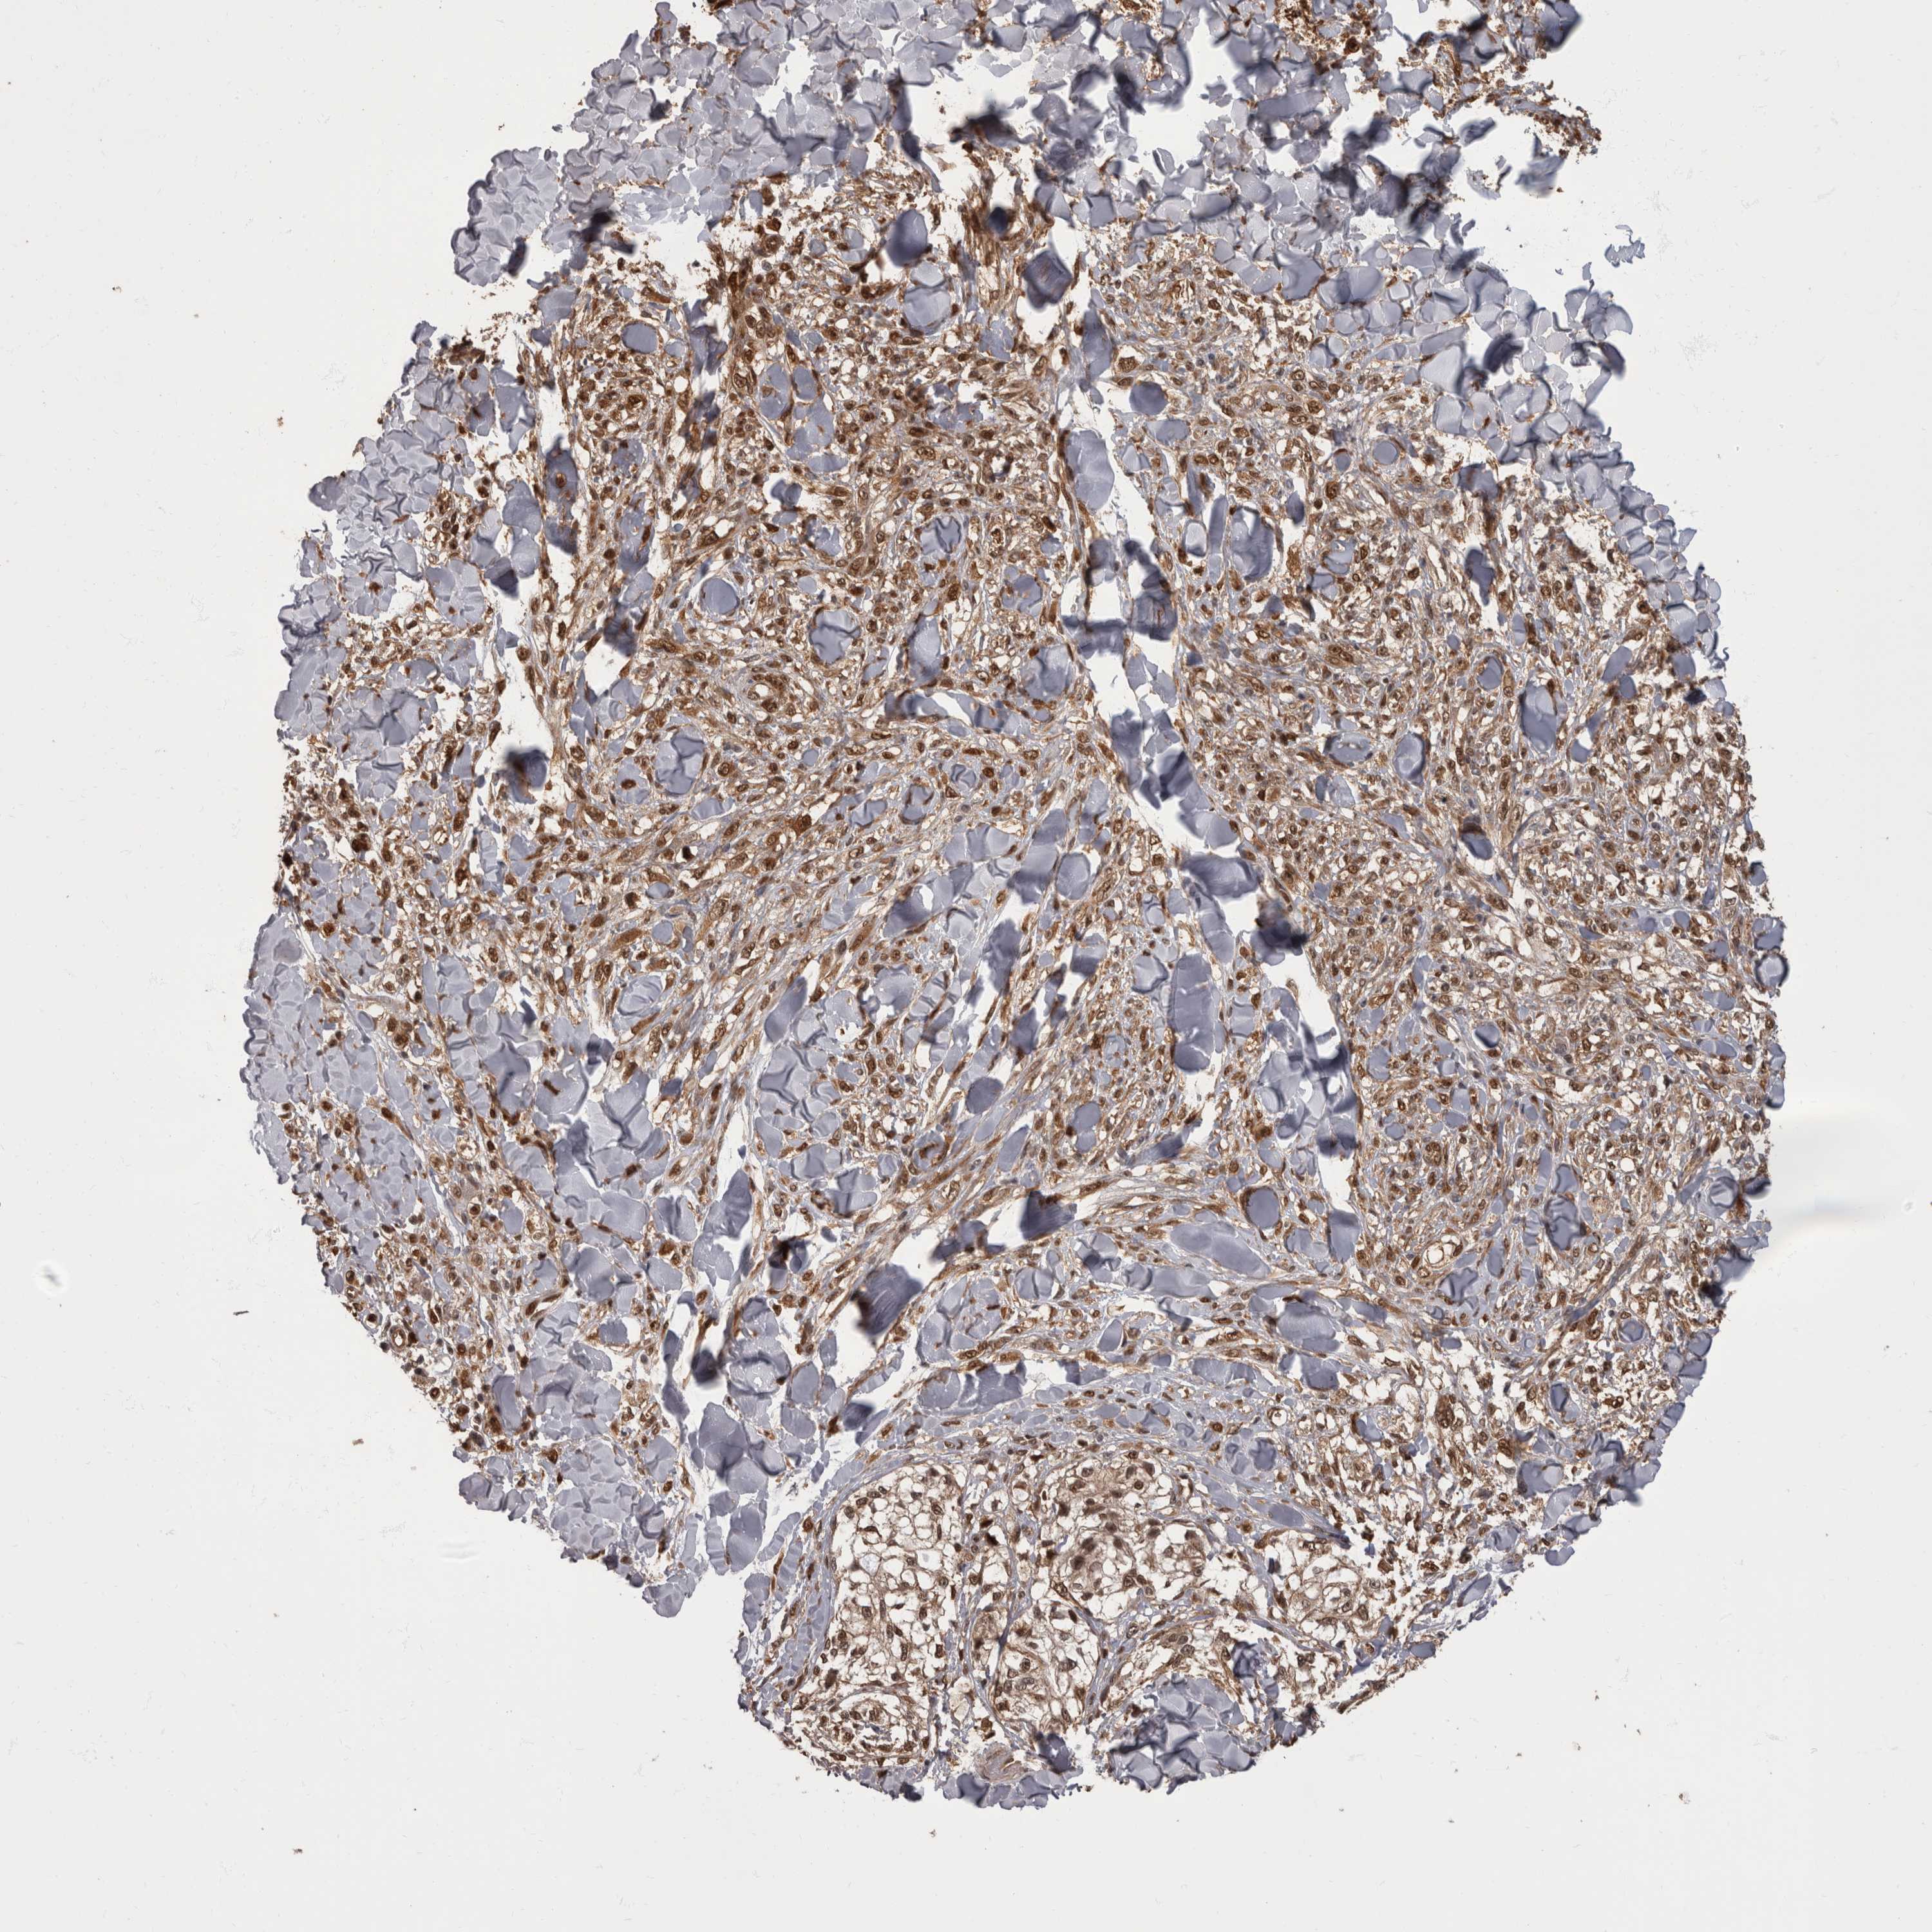

MELANOMA - Protein expressioni

A mouse-over function shows sample information and annotation data. Click on an image to view it in a full screen mode. Samples can be filtered based on level of antibody staining by selecting one or several of the following categories: high, medium, low and not detected. The assay and annotation is described here.

Note that samples used for immunohistochemistry by the Human Protein Atlas do not correspond to samples in the TCGA dataset.

Antibody stainingi

Antibody staining in the annotated cell types in the current human tissue is reported as not detected, low, medium, or high, based on conventional immunohistochemistry profiling in selected tissues. This score is based on the combination of the staining intensity and fraction of stained cells.

Each image is clickable and will lead to virtual microscopy that enables deeper exploration of all samples and also displays staining intensity scores, fraction scores and subcellular localization as well as patient and tissue information for each sample.

Antibody HPA026441

Antibody CAB013090

Staining

High

Medium

Low

Not detected

Intensity

Strong

Moderate

Weak

Negative

Quantity

>75%

75%-25%

<25%

None

Location

Nuclear

Cytoplasmic/membranous

Cytoplasmic/membranous,nuclear

Malignant melanoma, NOS

Malignant melanoma, Metastatic site